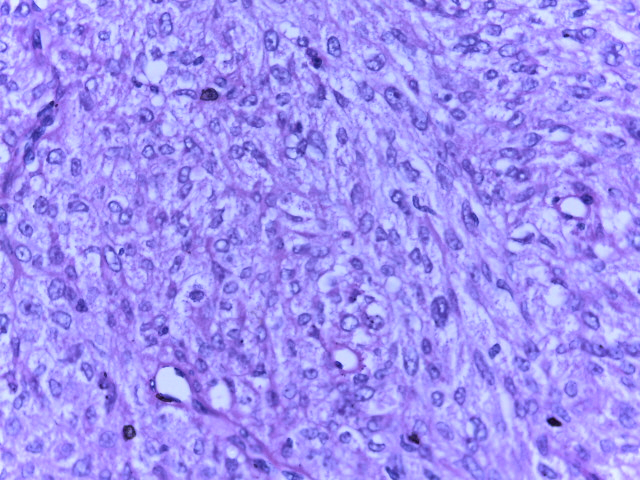

Diagnóstico:

Tumor del estroma gastrointestinal en orbita y agregar la referencia : Orbit. 2012 Apr;31(2):129-31.